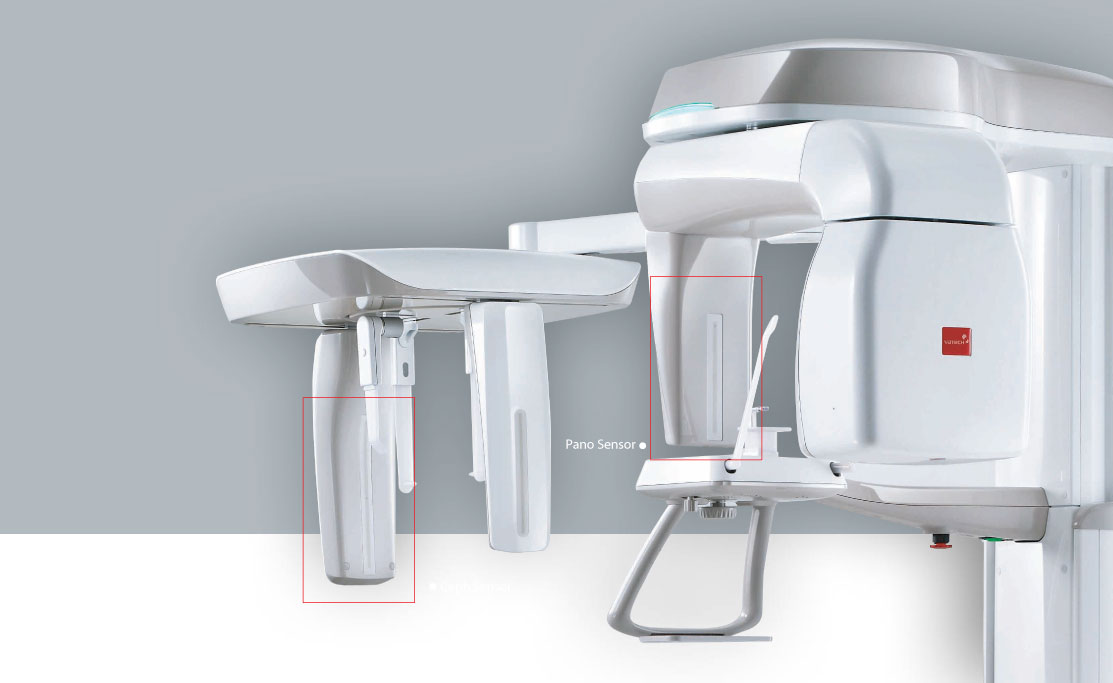

TWO DEDICATED SENSORS

The PaX-i offers two dedicated and embedded sensors for Pano and Ceph.This not only allows you to capture an optimal image from each sensor,but it also creates an effcient work ow.

PaX-i OPG

TWO DEDICATED SENSORS

The PaX-i offers two dedicated and embedded sensors for Pano and Ceph.This not only allows you to capture an optimal image from each sensor,but it also creates an effcient work ow.